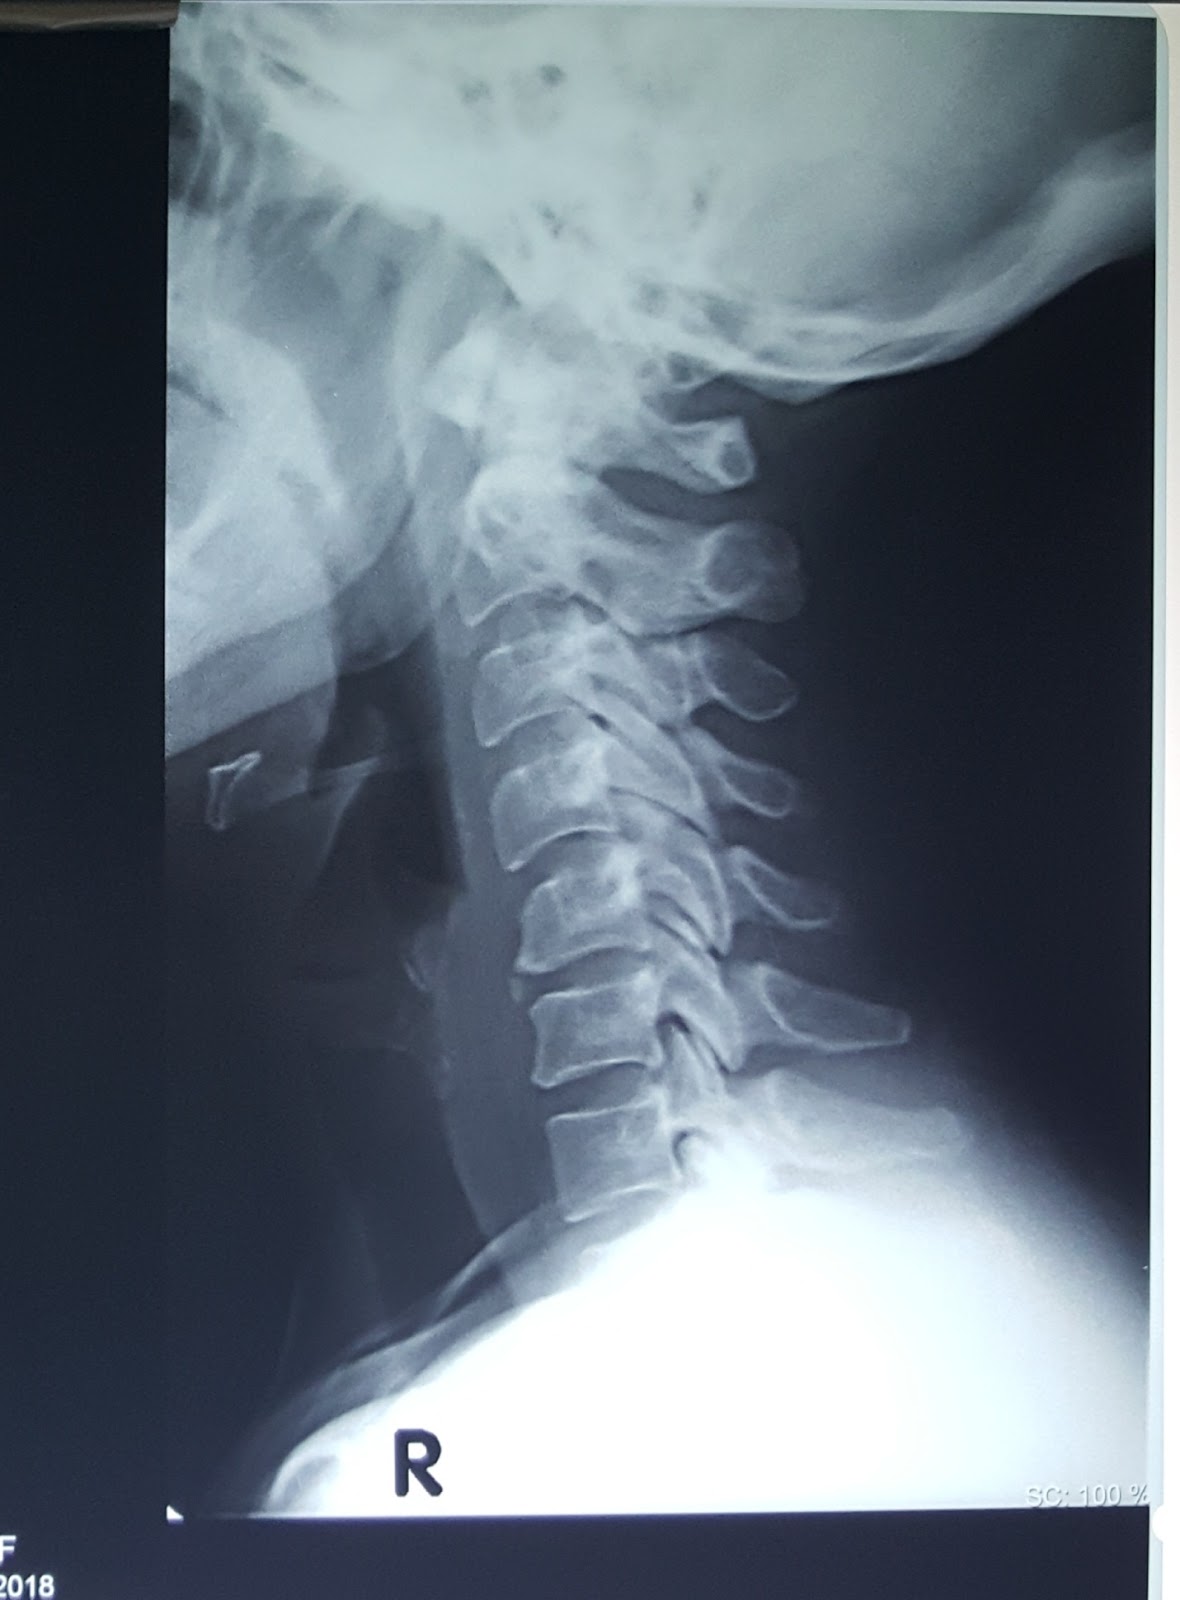

Vertebra cervicalis: строение и функции шейного позвонка